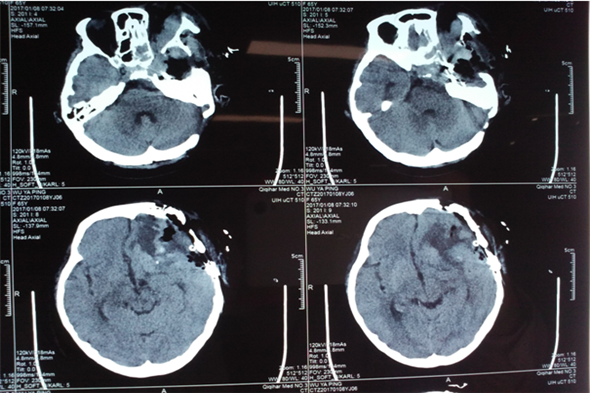

1月7日,麻醉医生顺利麻醉,手术室护士密切配合,手术由神经外二科吴卫东主任主刀,吴主任凭借精湛的手术技能,术中探寻蝶骨脊、颞骨岩部及斜坡处,行电烧并切断供血。手术中,由于患者病情重,骨质受侵蚀,酥脆明显,导致出血较多。吴主任当机立断,切断根部后再于显微镜下寻找到边界逐步分离并分块切除肿瘤组织,由于肿瘤长度达9cm,前方达前颅窝底,内侧达右侧蝶骨脊,后方达颞极下部,并在眶后壁切除了部分肿瘤组织,根据肿瘤颜色及质地以及侵蚀程度考虑恶性脑膜瘤可能性大。手术进行的很顺利,术后第一天患者即意识清醒,无功能缺失。如此喜人的结果,令所有神经外二科的医护人员倍感欣慰。

术后第一天CT